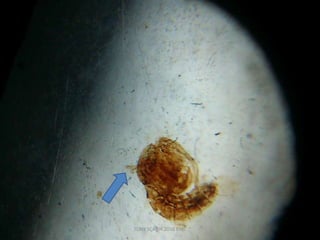

LIFE CYCLE-PUPA

• Non feeding stage/resting stage

• Comma shaped

• Cephalothorax and segmented abdomen

• Two small respiratory tubes or trumpets :upper

surface of the thorax.

• Stay quiet at water surface